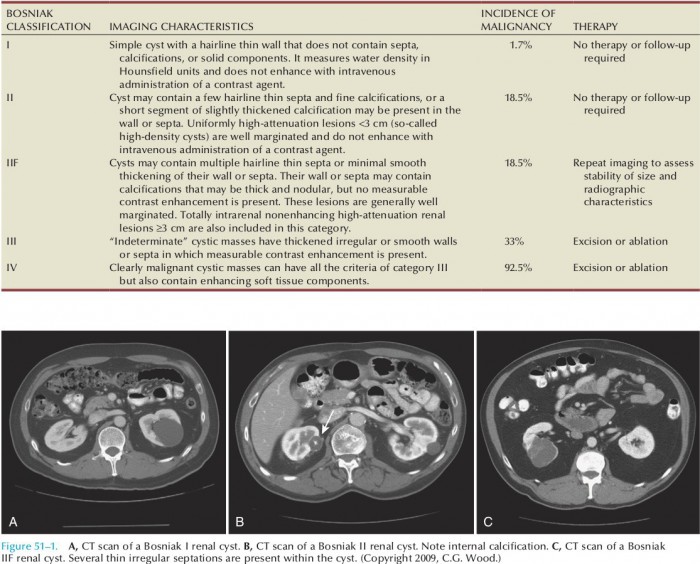

При прохождении МРТ или КТ четко видна ее однокамерность. Категорию составляют простые кисты. Часто образуются в почках, но при этом не являются угрозой. Как правило, характеризуется тонкой перегородкой. Стенки без утолщений и отложений солей. Формации этой категории не требуют дальнейшего наблюдения или лечения, поскольку являются доброкачественными.

Сюда относятся несложные кисты. В отличие от предыдущей группы возможно небольшое утолщение стенок, а также наличие незначительных кальцификатов. При обследовании может быть выявлено несколько тонкостенных перегородок. Группу также составляют плотные образования с четкими контурами размером меньше 3 см. Являются доброкачественными, лечения не требуют.

Уплотнения характеризуются увеличением полости, утолщением стенок между перегородками, возможны узелковые отложения кальция на них. При обследовании вводимый контраст не виден. Кисты однородной плотности и размерами больше 3 см также входят в эту категорию. Они еще попадают под признаки доброкачественности, но уже требуют наблюдения. Малый процент таких образований числится раковыми.